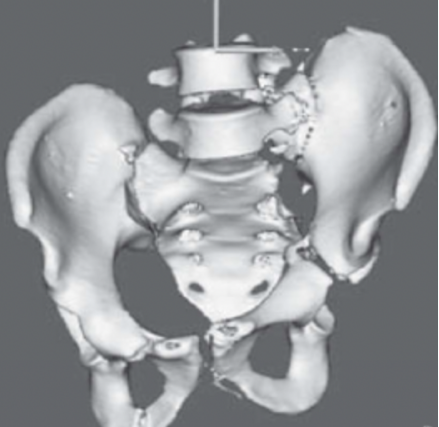

术后骨盆CT三维重建影像显示骨盆环较术前明显改善。(图4)